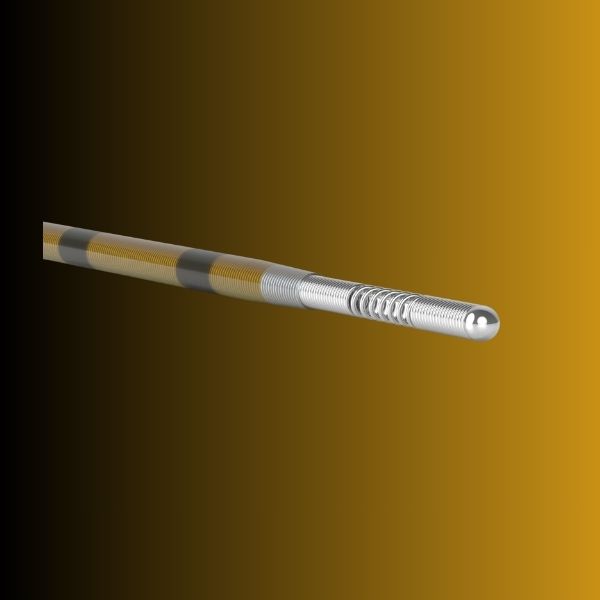

Η τεχνική εφαρμόζεται με τον ασθενή σε πρηνή θέση, με τοπική αναισθησία στο σημείο παρακέντησης και υπο ακτινοσκοπική καθοδήγηση. Μια ειδική βελόνα εισάγεται στον επισκληρίδιο χώρο μέσα από το ιερό τρήμα και χορηγείται σκιαστική ουσία για να σκιαγραφηθούν οι νευρικές ρίζες. Η εικόνα που λαμβάνεται με την ακτινοσκοπική λήψη λέγεται επισκληριδιογράφημα. Οι παγιδευμένες ρίζες δεν προσλαμβάνουν σκιαστικό, μια και το υγρό ακολουθεί τον πιο εύκολο δρόμο, με τη λιγότερη αντίσταση. Στις περιοχές που δεν σκιαγραφείται η νευρική ρίζα, κατευθύνεται δια μέσω της ειδικής βελόνας παρακέντησης ο καθετήρας Racz και γίνεται μηχανική συμφυσιόληση και στη συνέχεια εγχύεται πάλι σκιαστικό για την επιβεβαίωση της διάνοιξης του χώρου (σκιαγραφείται η νευρική ρίζα ) και εγχύονται θεραπευτικές ουσίες όπως κορτικοστεροειδή, τοπικό αναισθητικό και υαλουρονιδάση που προκαλεί χημική συμφυσιόληση.